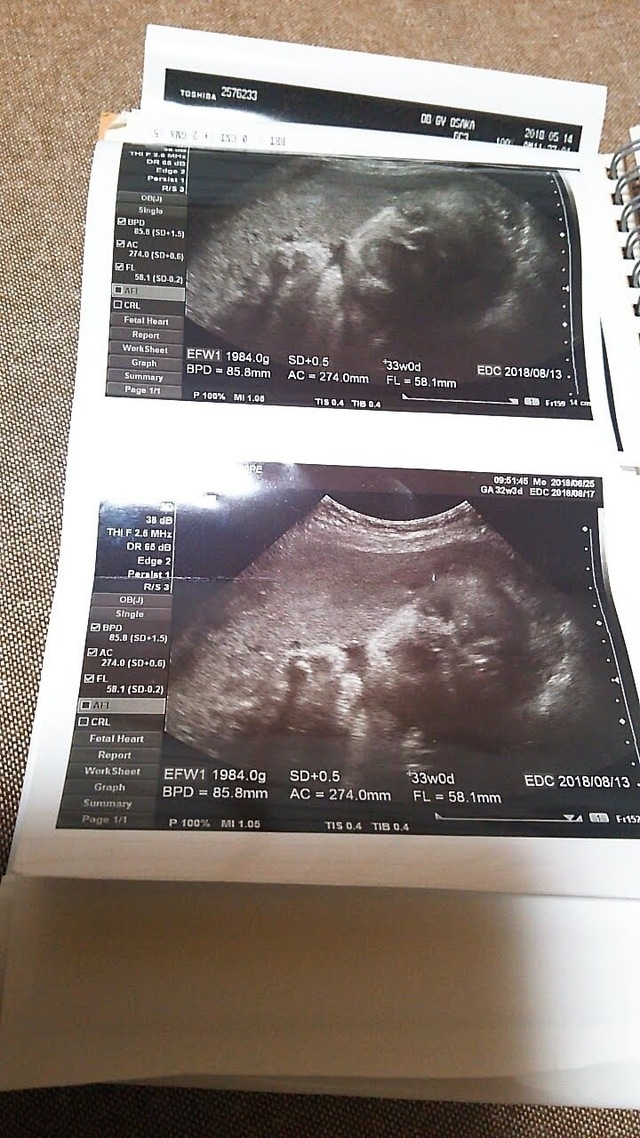

32週0日(32w0d・男の子)|natsu0901 さん(24歳)

エコー写真撮影時のエピソード:

エコーを見る時に先生がお腹を触ると顔をしかめたのをよく覚えています。嫌だったのかなと笑って話していました。顔をあまり見せてくれなくて、やっと見れたお顔でした。この時に妊娠中毒症になり、高血圧になりむくみもひどく入院しました。